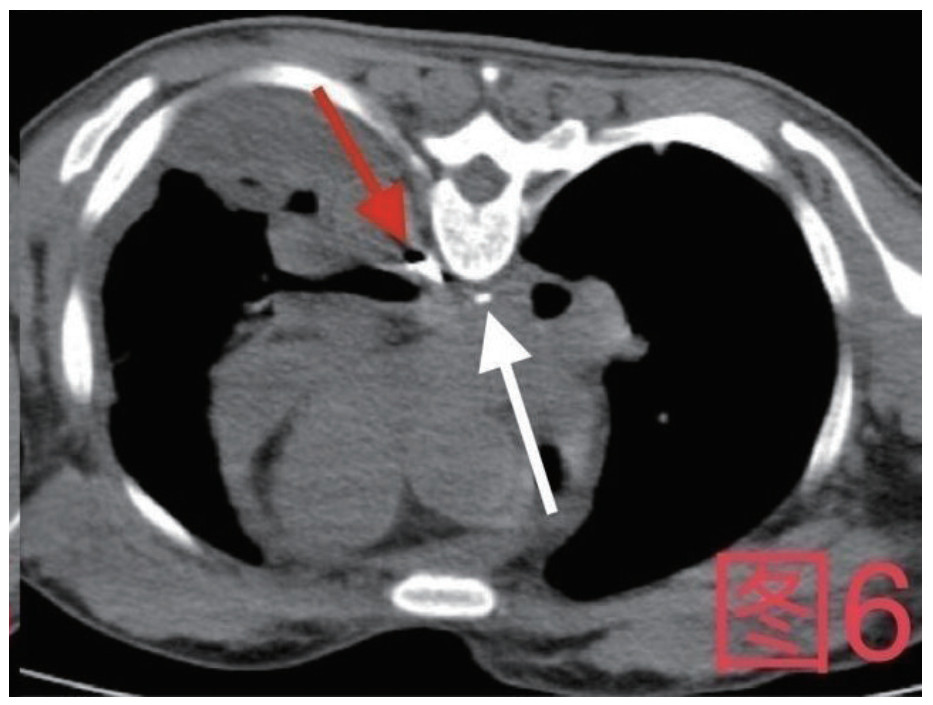

患者,女,41岁,2020年10月26日因“腹痛3 d”入急诊,否认近期有吞服异物、鱼刺、骨头等,无腹部手术史。入院查体:体温36.9℃,心率115次/min,血压98/57 mmHg(1 mmHg=0.133 kPa),血氧饱和度:97%;腹软,上腹部压痛,腹肌略紧张,余查体阴性。入院初检验:乳酸13.3 mmol/L;超敏C反应蛋白212.46 mg/L;血常规白细胞计数35.0×109/L,中性粒细胞百分数0.908,降钙素原50.46 ng/mL;Pro-B型钠尿肽7 117 pg/mL;肌钙蛋白T 0.147 ng/mL;肌酐554 μmol/L,谷丙转氨酶2 499 U/L,谷草转氨酶5 908 U/L。心电图未见ST-T改变;胸腹部增强CT(图 1、图 2):示大量心包积液伴少许积气,纵隔少量积气;左侧少量胸腔积液,右肺下叶感染,盆腔少量积液;心脏超声:心包积液(大量),最深处21 mm;急诊予心包穿刺引流出大量浑浊脓性液体,心包穿刺引流液常规:中性粒细胞占96%,涂片见革兰阴性杆菌及革兰阳性球菌,积液培养见咽峡炎链球菌。诊断:化脓性心包炎,脓毒血症,多脏器功能不全,代谢性酸中毒。本病例报道经温州医科大学附属东阳市人民医院伦理委员会批准,且所有临床检测指标及有创操作均获得家属同意或直系亲属的授权(伦理审批号:东人医2021-YX-124)。

| 图 1 箭头所指为心包内积气积液 |

治疗经过:急诊予美罗培南0.5 g,1次/12 h抗感染,补液支持,心包引流等治疗措施,收住感染科后继续抗感染治疗,期间心包积液培养出白假丝酵母菌,加用氟康唑200 mg,1次/d, 口服,心包积液、左侧胸腔积液引流等措施,治疗10 d后复查胸部CT仍有中大量心包积液伴少许积气,纵隔积气;左侧少量胸腔积液,两肺叶间裂少许积液。对照前片(2020.10.26)心包积气及左侧胸前积液有增多,叶间裂积液新发,心包积液略有减少。右肺下叶感染,左肺下叶膨胀不全,较前右肺下叶感染有吸收,左肺下叶膨胀不全新发。考虑不能排除食管纵隔瘘,予口服碘海醇后胸部CT检查(图 3~6):约胸6椎体水平食管纵隔瘘,瘘口为相应水平食管壁右前方可能;胃镜(图 7):食道距门齿25 cm右后壁见一直径约1.0 cm凹陷,内有一小瘘口。胃镜下予钛夹2枚夹闭瘘口(图 8),同时植入空肠营养管。至此患者病情明确诊断食管心包瘘,患者经以上治疗后心包积液、胸腔积液逐渐减少,于11月13日拔除心包及胸腔引流管,因患者签字回当地就诊,予口服莫西沙星、氟康唑带药出院,出院后随访,患者未回当地医院治疗,仅在家中继续空肠营养管饲喂及口服抗菌药物治疗。

| 图 6 患者俯卧位,白色箭头为纵隔内碘海醇,红色箭头为食管内碘海醇 |